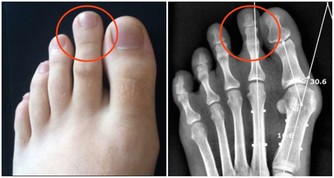

不少人喜歡在辦公桌上放一些像布洛芬或萘普生這樣的止痛藥。確實,當頭痛、背痛或腰痛時,這些非甾體類抗炎藥物可以讓你舒服一些。但長期服用高劑量止痛藥,不僅會出現胃腸道問題(噁心、便秘),還可能有更嚴重的並發症,如潰瘍甚至腎衰竭。當然,疼痛的時候你也沒必要硬扛著,只要嚴格按標籤服用即可。然而,如果服用超過10天,最好看醫生。